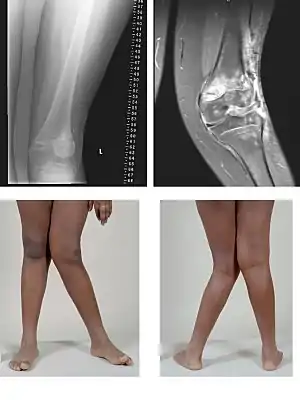

| Valgus Deformity MRI and photograph | |

Knee arthritis with valgus knee

Rheumatoid knee commonly presents as valgus knee. Osteoarthritis knee may also sometimes present with valgus deformity though varus deformity is common. Total knee arthroplasty (TKA) to correct valgus deformity is surgically difficult and requires specialized implants called constrained condylar knees.